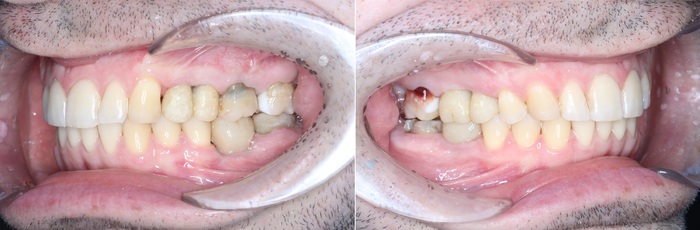

Когда же вы уже поймете, что для удаления подобных зубов:

требуется 20 минут, а никак не трехчасовой наркоз и трое суток в стационаре. (подобный случай я описывал подробнее в этой статье)

А для таких:

Чуть меньше часа (отдельно верх, отдельно низ):

В данном случае я очень долго и подробно рассказывал молодому человеку обо всех возможных осложнениях, особенностях восстановления и дальнейшем протезировании. Более того, я планирую написать полноценную статью по этому клиническому случаю, когда у пациента будут стоять имлантаты.